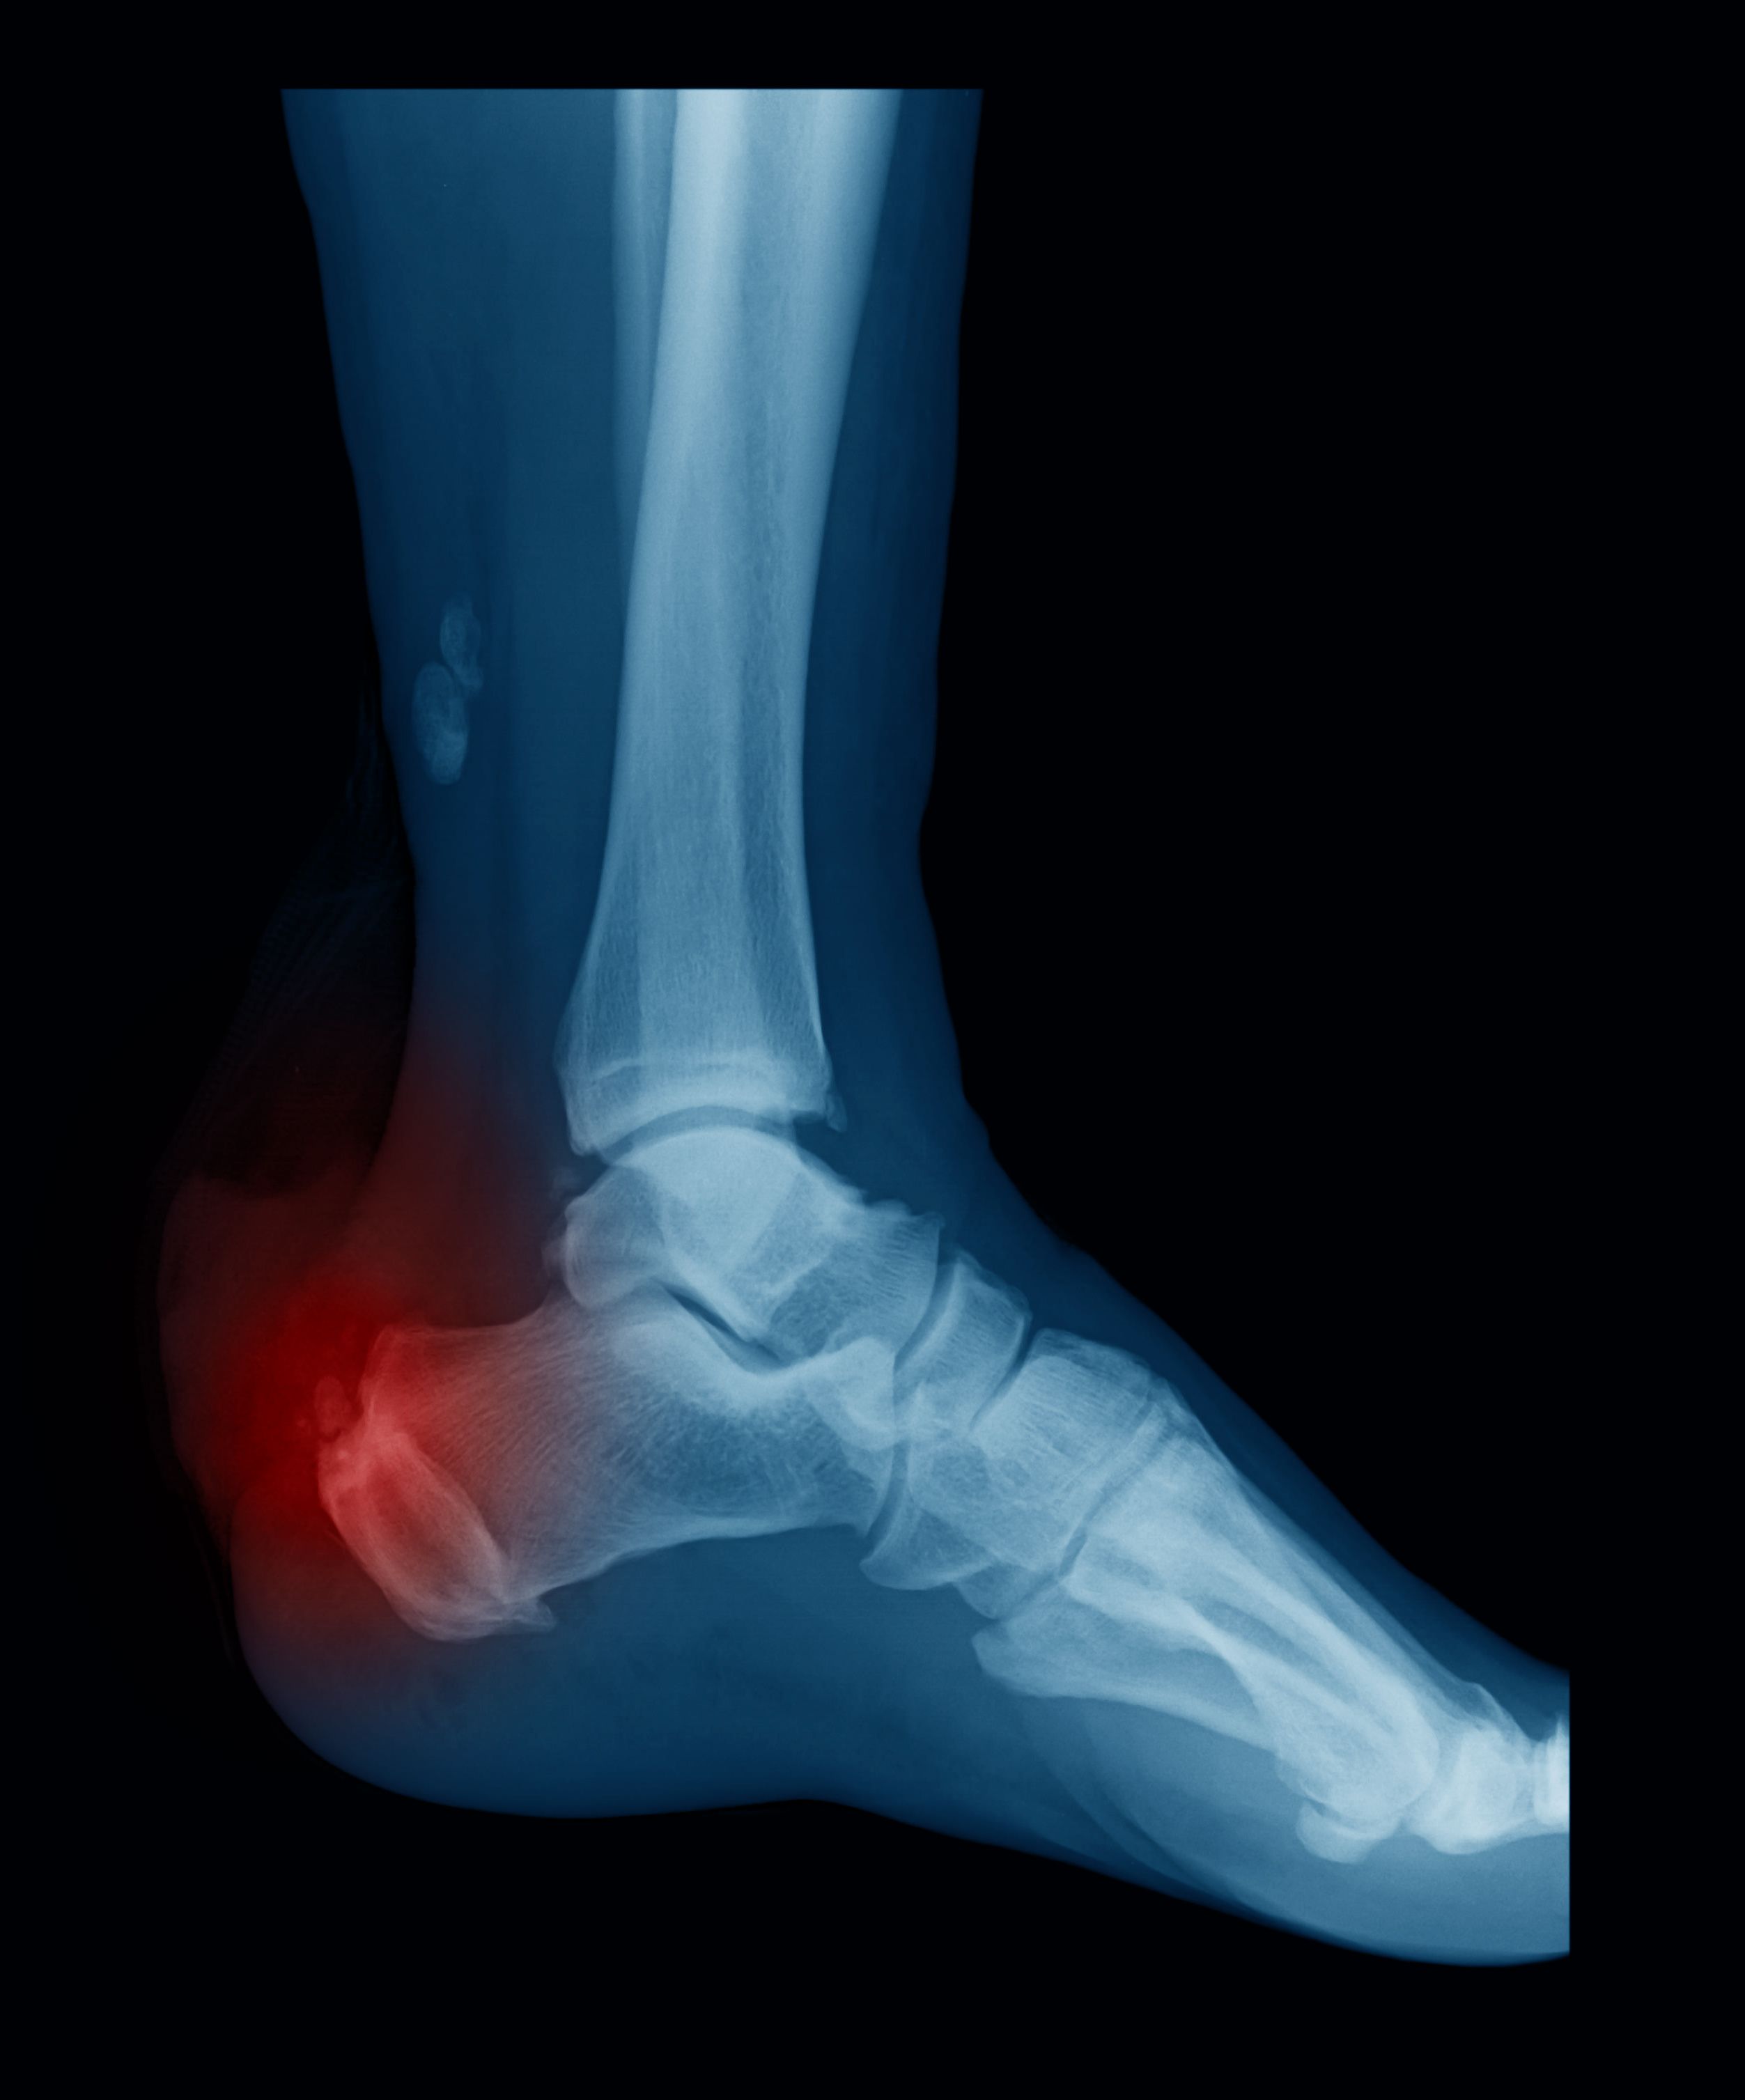

The High Stakes of an Achilles Injury

Achilles tendon injuries can have serious, sometimes catastrophic, impacts on an athlete’s career, as well as their long-term physical and mental health. “The impact of an Achilles rupture is significant,” explains Julie Campbell, DU associate vice chancellor and deputy athletic director for Pioneer Health and Performance. “In some cases, it can be 9 to 12 months before they can return to competitive-level sport, if ever.”

Campbell, a designated DU athletics health care administrator with primary day-to-day medical care oversight for the women’s gymnastics team, notes that even less-severe Achilles injuries can cause serious health and performance ramifications, taking an athlete out of their sport for weeks or months.

Although this research is immediately relevant to athletes, its potential extends across the medical field. “The Achilles tendon is absolutely paramount for gait, jumping, landing, walking — a lot of activities of regular human movement,” explains Sabick. A recent scientific study from the University of Ottawa demonstrates that in the last decade, incidents of Achilles tendon injuries among US Adults have increased significantly, particularly affecting adults over 30. Both in and out of professional sports contexts, it is vital to understand how this essential and vulnerable tendon functions so that more people can mitigate and eliminate injuries.